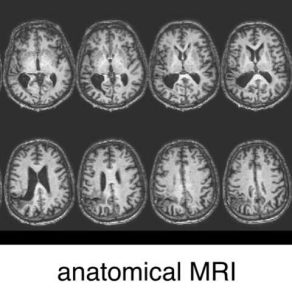

(Ictus-Immagine: esempio di immagini anatomiche (utilizzate anche dai medici) per mostrare la posizione e l’entità del danno da ictus. Credito:…